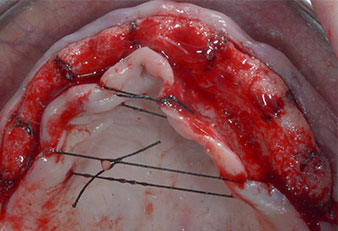

Due to the relatively hard bone (D2) in this area, the 10 mm long implant sites at positions 11 and 21 were finalized with a 4 mm diameter rotary drill, in combination with a W&H WS-75 L surgical contra-angle handpiece, the W&H Implantmed implant motor and the optional W&H Osstell ISQ module. In contrast, due to the soft bone the posterior sites were prepared to a final 3 mm diameter using the Piezomed I3P instrument. The implants were finally placed transgingivally to osseointegrate for three months (Figs. 6-10). The existing denture was retained on four provisional implants (Fig. 8).